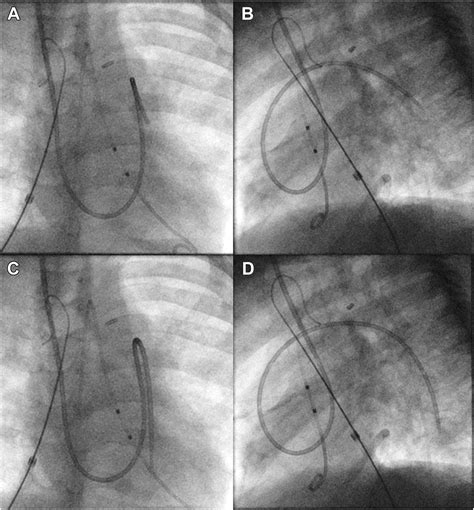

The Pulmonary Artery Wedge Pressure (PAWP) is a measurement obtained during a right heart catheterization procedure. It reflects the pressure in the left atrium of the heart, which is crucial for assessing the function of the left ventricle. By inserting a catheter into the pulmonary artery and advancing it until it wedges into a small branch, clinicians can measure the pressure, which is then used to estimate the left atrial pressure.

Measuring the Pulmonary Artery Wedge Pressure involves a right heart catheterization procedure. Here are the steps involved:

1. Patient Preparation: The patient is prepared for the procedure, which may include sedation and local anesthesia.

2. Catheter Insertion: A catheter is inserted into a large vein, typically the internal jugular or femoral vein, and advanced to the right atrium.

3. Advancing the Catheter: The catheter is then guided through the right ventricle and into the pulmonary artery.

4. Wedge Position: The catheter is advanced until it wedges into a small branch of the pulmonary artery, occluding blood flow.

5. Pressure Measurement: The pressure is measured at this point, which reflects the left atrial pressure.

6. Data Interpretation: The measured pressure is interpreted in the context of the patientโ€™s clinical condition to guide diagnosis and treatment.